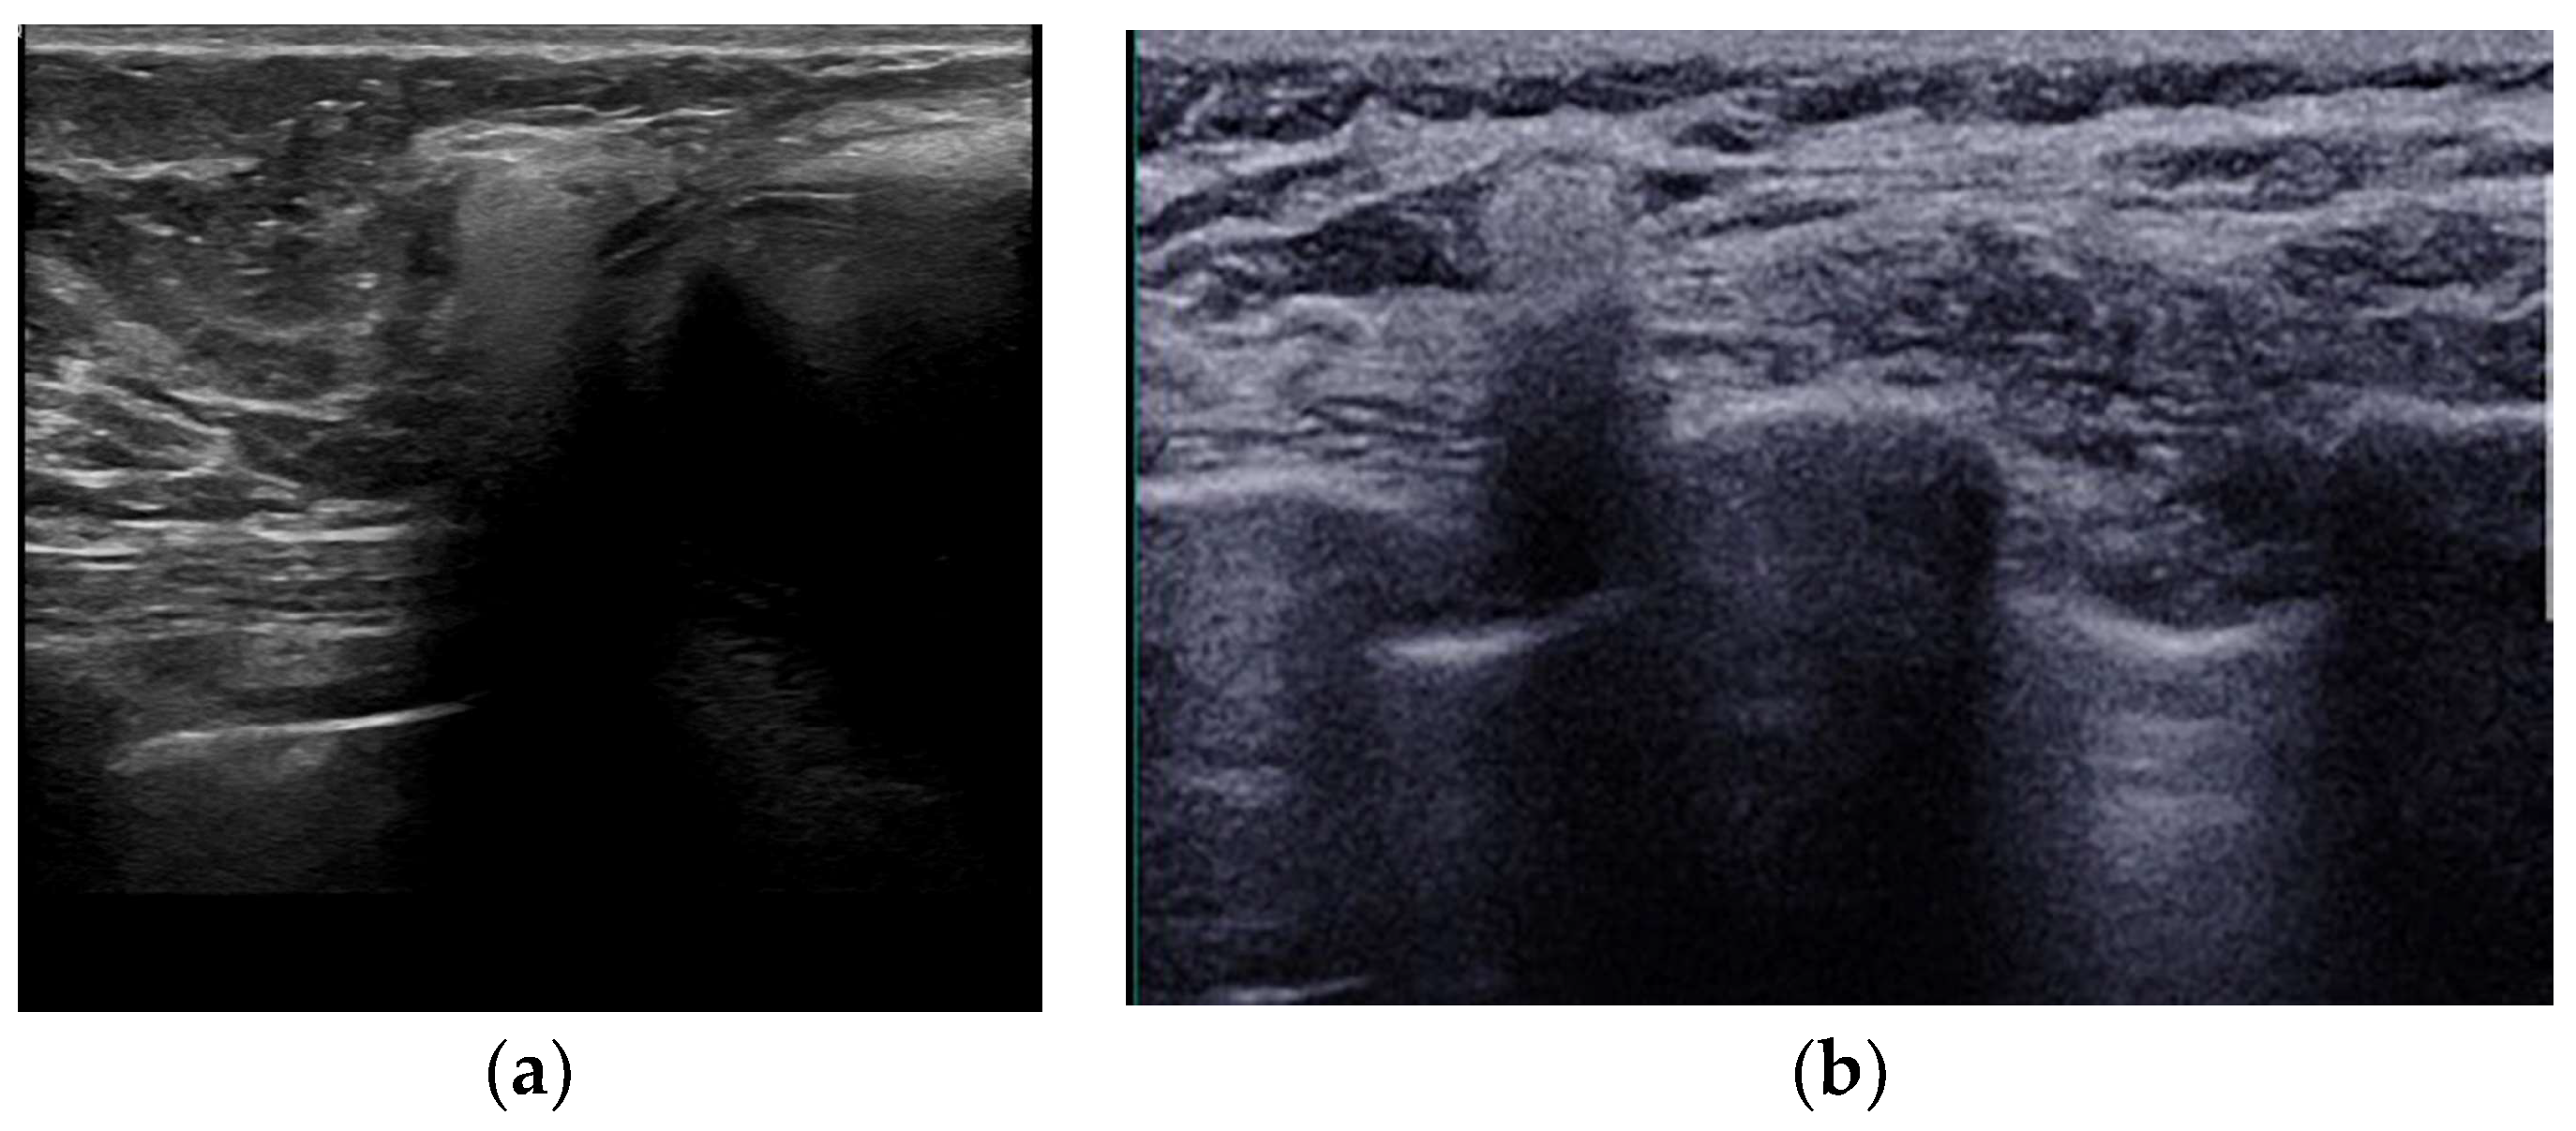

5.2.1. Seromas

5.2.2. Hematomas

5.2.5. Implant Rupture